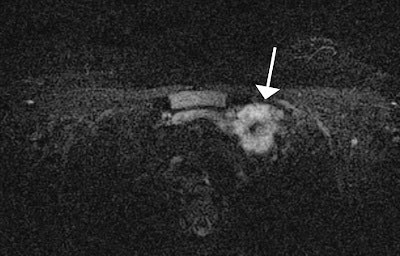

The MRI findings were compared with subsequent diagnostic procedures to differentiate malignant from benign lesions. The researchers detected 138 incidental findings in 107 of the 500 (21.4%) patients. The most common site was the liver (44.2%), followed by the lung (17.4%), mediastinum (15.9%), pleural cavity (10.9%), bone tissue (6.5%), spleen (2.2%), major pectoral muscle (2.2%), and kidney (0.7%).

Of the incidental findings, 18.1% were confirmed to be malignant. Malignant findings were exclusively detected in patients with known breast carcinoma, whereas incidental findings in patients without a history of carcinoma were all benign, according to Alduk and colleagues. Also, 24.8% of incidental findings among patients with history of breast cancer were malignant.

"Malignant lesions were exclusively detected in patients with previously known breast carcinoma, which emphasizes the importance of careful assessment of incidental findings in this group," the researchers added. "The present study showed that the prevalence of malignant findings in patients with a history of breast cancer is dependent on location, with the high likelihood of bone lesions being malignant (100%) in comparison to other locations."

Bone lesions are more likely to be malignant in comparison with other locations, probably because of the wide spectrum of benign abnormalities encountered in the liver (cysts and hemangiomas) or pleural cavity (effusions). Thus, a new bone lesion in a patient with breast carcinoma should be considered malignant until proved otherwise and should prompt further diagnostic workup. Also, 11.6% of hepatic lesions were metastatic, altering further treatment, so indeterminate lesions that do not satisfy the criteria for cysts or hemangiomas require further diagnostic workup (using ultrasound, CT, or liver MRI).